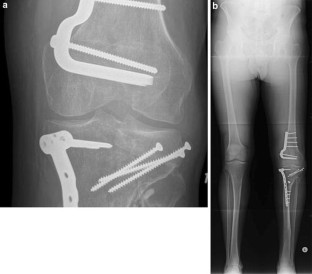

This study was conducted to examine the long-term survivorship and functional outcome of distal femoral varus osteotomy with fresh osteochondral allograft following failed lateral tibial plateau fracture surgery. We hypothesized that this procedure would be associated with a low rate of conversion to total knee arthroplasty (TKA) at medium to long-term follow-up.

A consecutive series of 27 of distal femoral varus osteotomy combined with fresh osteochondral allograft following (27 patients) conducted between January 1981 and January 2005 for failed lateral tibial plateau fracture was retrospectively reviewed. Outcome measures included the Knee Society Knee Score (KSKS) and Knee Society Function Score (KSFS) and conversion rates to TKA.

The study group consisted of 15 females (55.6 %) and 12 males (44.4 %), with a median age of 41.2 years (range 17–62 years). The median follow-up was 13.3 years (range 2–31 years). The knee function scores improved significantly at 2 years post-surgery (p < 0.01) from a median of 54.6 points preoperatively to 83.8 points (KSKS) and median of 50.6 points to 71.1 points (KSFS) at 2 years post-distal femoral varus osteotomy with fresh osteochondral allograft following surgery. At most recent follow-up, 4/27 patients had required conversion to TKA, and one patient had fractured the FOCA, requiring revision of the allograft. The survivorship for distal femoral varus osteotomy with fresh osteochondral allograft following was 88.9 ± 4.6 % at 10 years, 71.4 ± 18.1 % at 15 years, and 23.8 ± 11.1 % at 20 years.

The use of distal femoral varus osteotomy combined with fresh osteochondral allograft following in patients with failed lateral tibial plateau fracture results in the majority of patients having good or excellent clinical outcomes and significantly delays the need for TKA in most patients.